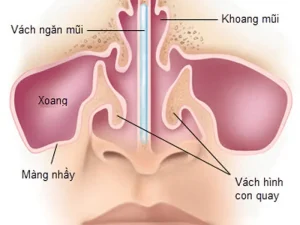

Bệnh nhiễm trùng đường hô hấp: Tổng quan về nguyên nhân, triệu chứng, cách điều trị và phòng ngừa hiệu quả để bảo vệ lá phổi của bạn

Chào bạn, hôm nay chúng ta sẽ cùng nhau tìm hiểu về một nhóm bệnh lý rất phổ biến mà hầu như ai cũng đã từng mắc phải ít nhất một lần trong